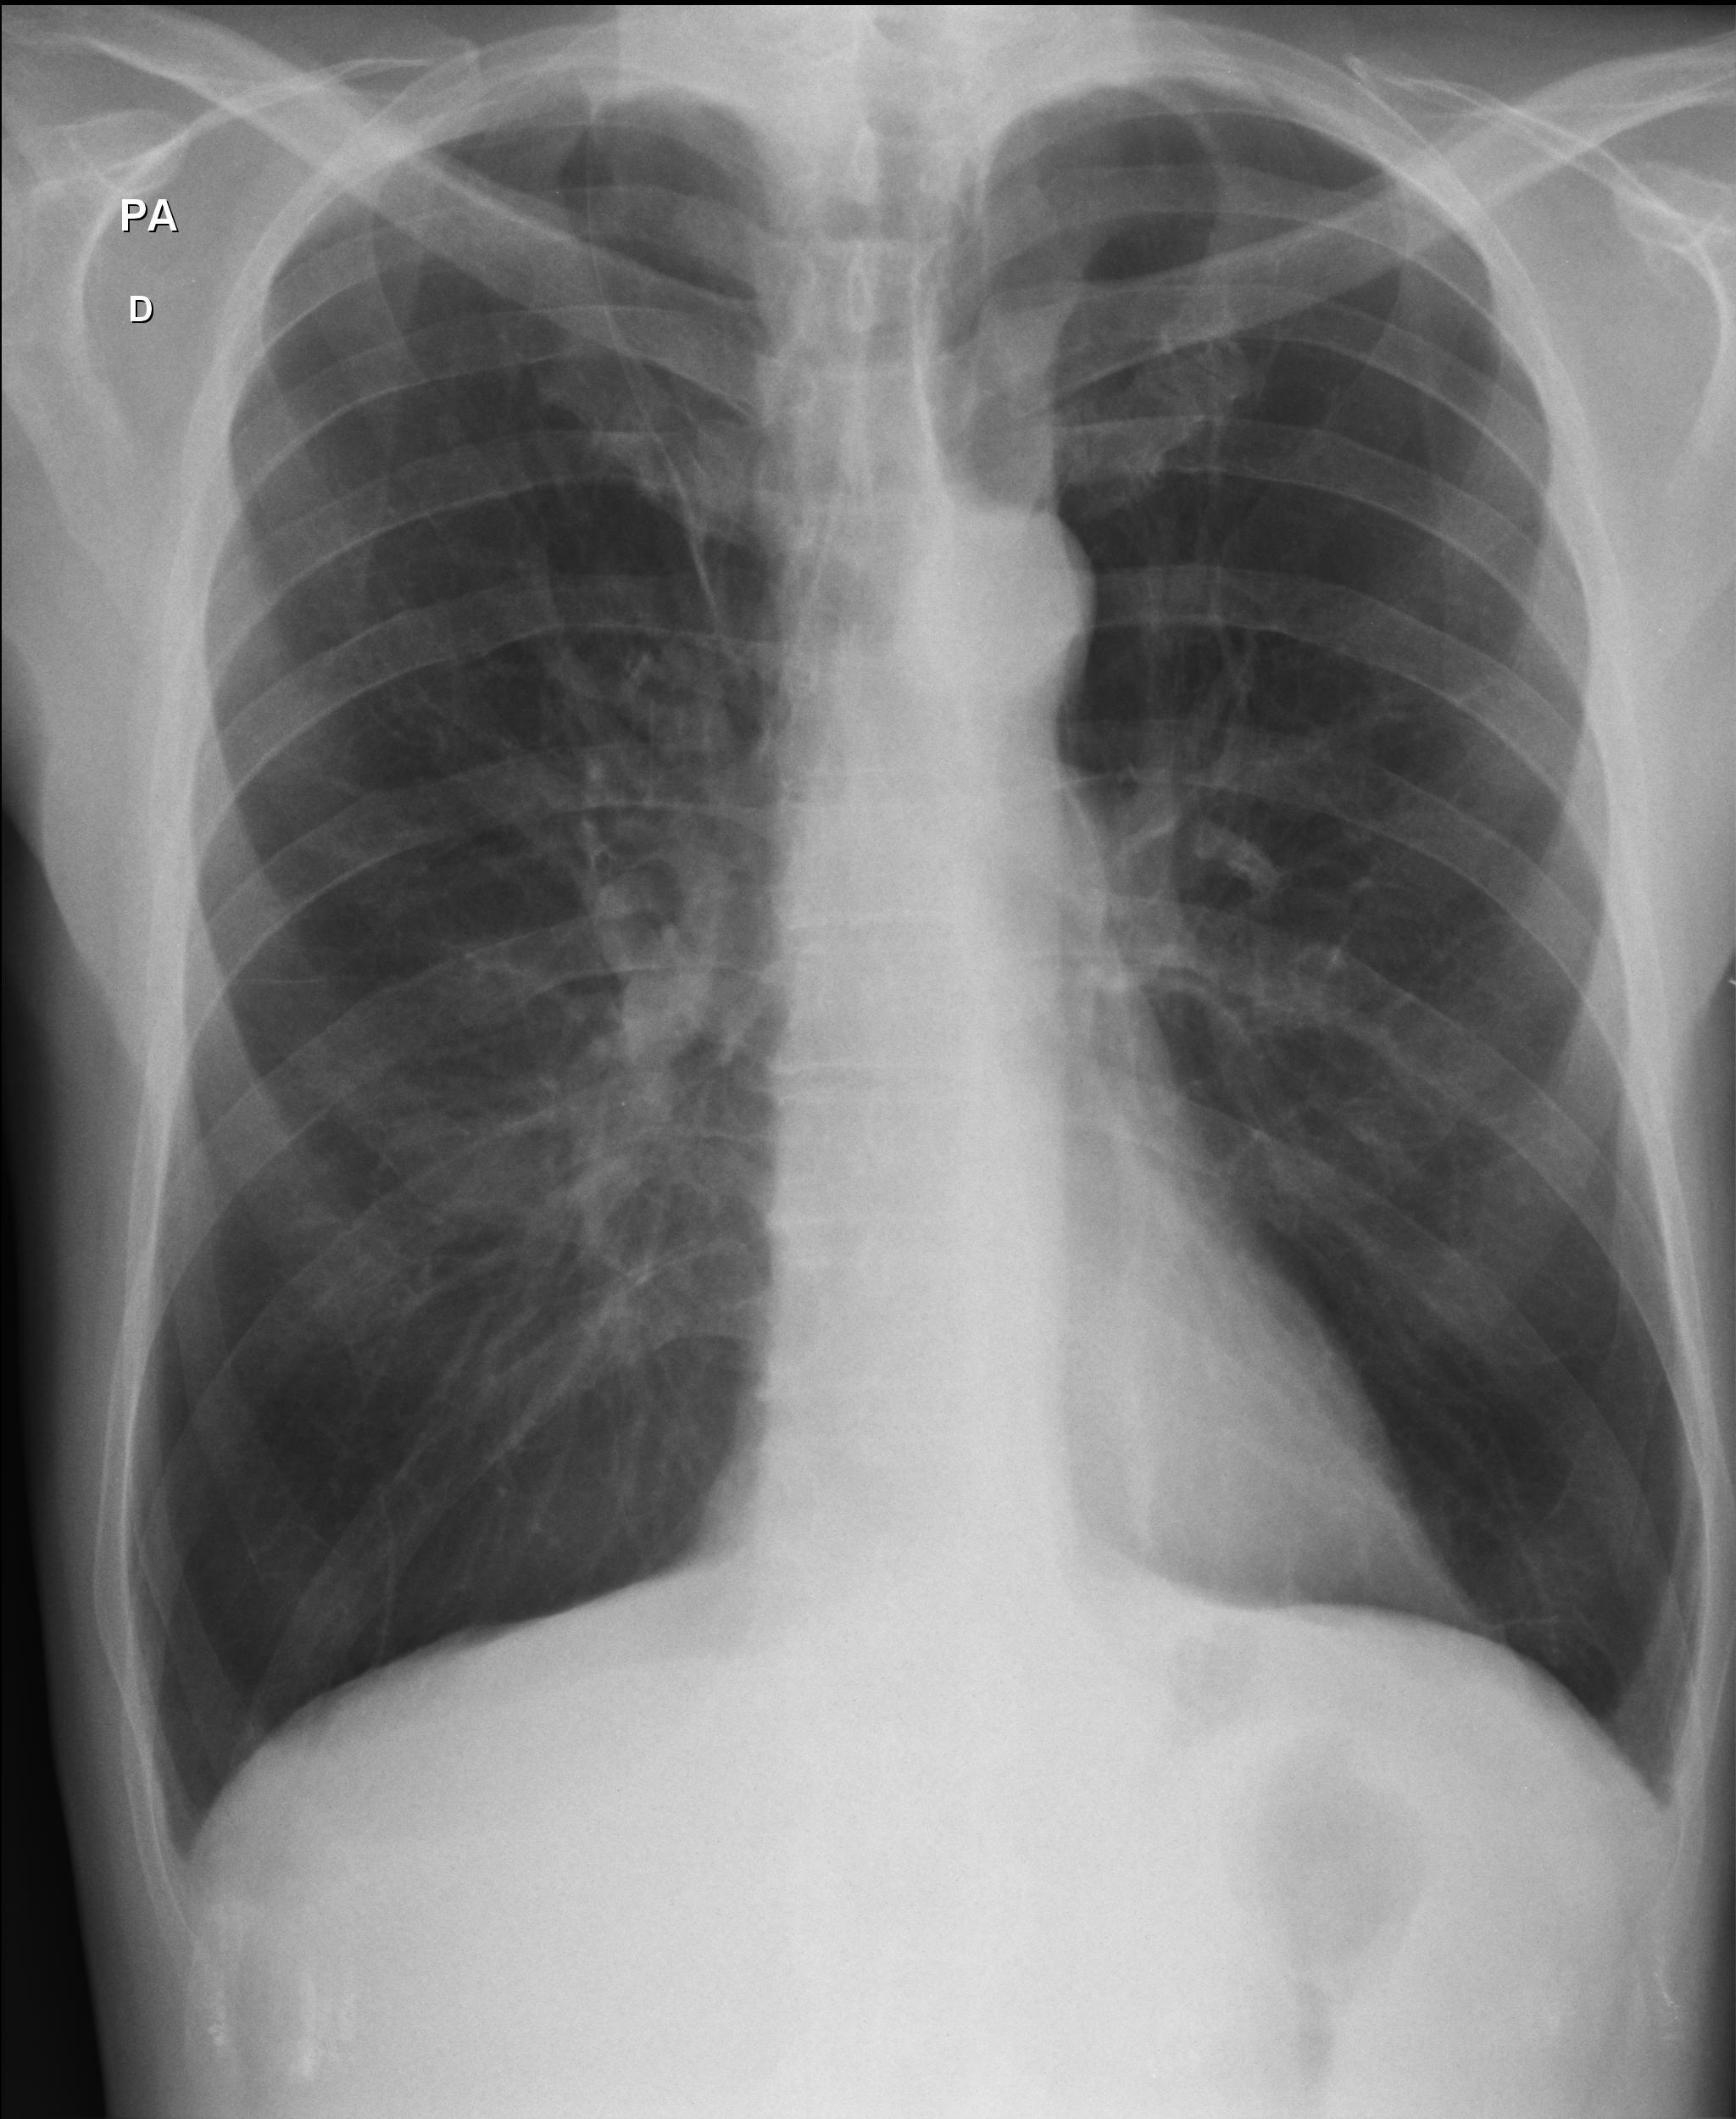

Caso relatado na Reunião de Discussão de Casos Clínicos do Hospital Universitário Prof. Polydoro Ernani de São Thiago, iniciada pelos Profs. Jorge Dias de Matos, Marisa Helena César Coral e Rosemeri Maurici da Silva, em julho de 2017. No dia 14 de junho de 2018, no auditório do HUPEST, realizou-se a apresentação e discussão do caso cujo registro é apresentado a seguir. Trata-se da discussão de onze casos em radiologia torácia, de forma interativa com a plateia, e assim ocorre também neste artigo.